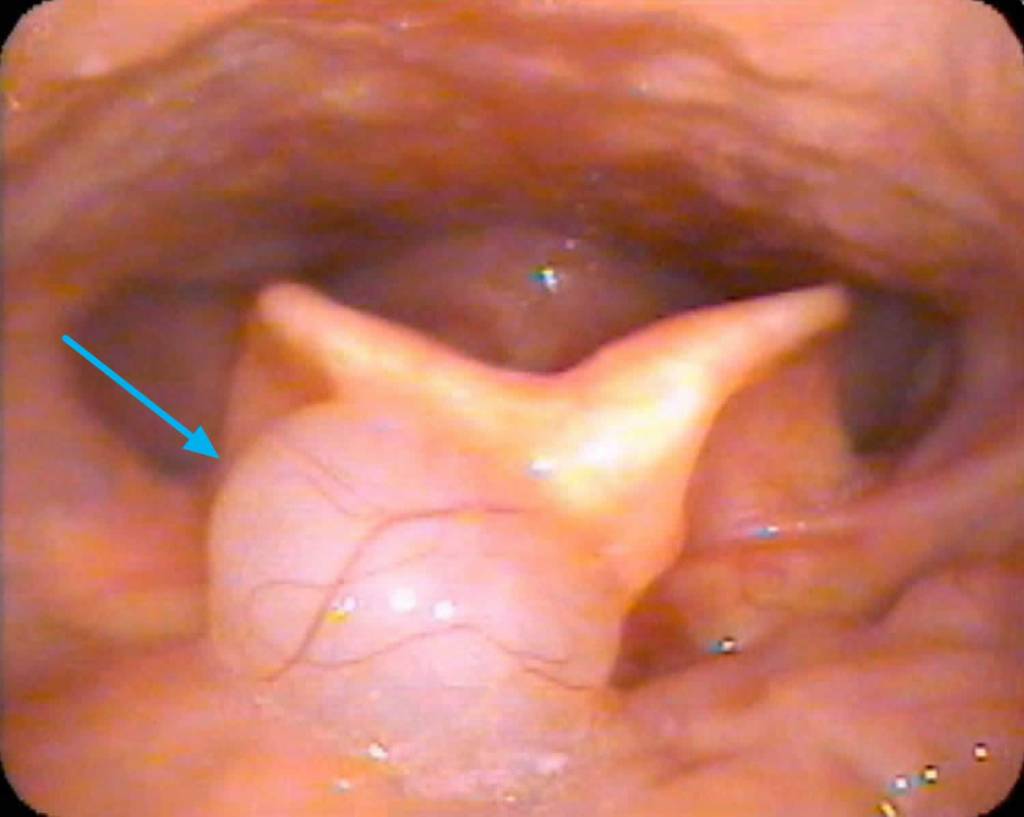

Diagnostic Flexible Nasopharyngolaryngoscopy (FNPLS) is a procedure used to visualize the larynx and assess the structural integrity of the tissues. During the procedure, a flexible scope is inserted through the nose or mouth and passed down into the throat to reach the larynx. This allows the healthcare provider to directly observe the larynx and identify any abnormalities.

In the case of laryngomalacia, laryngoscopy often reveals specific findings that confirm the diagnosis. The most common finding is the collapse of the supraglottic structures, which include the epiglottis, aryepiglottic folds, and false vocal cords. These structures may appear floppy, redundant, and prolapsed, leading to partial obstruction during breathing. The degree of collapse can vary, ranging from mild to severe.

In addition to assessing the structural aspects, laryngoscopy may also help identify any other associated conditions or anatomical abnormalities (secondary airway lesion/SAL) that could contribute to the symptoms. It allows the healthcare provider to evaluate the movement of the vocal cords, assess the presence of any anatomical obstructions, and determine the overall impact on breathing.